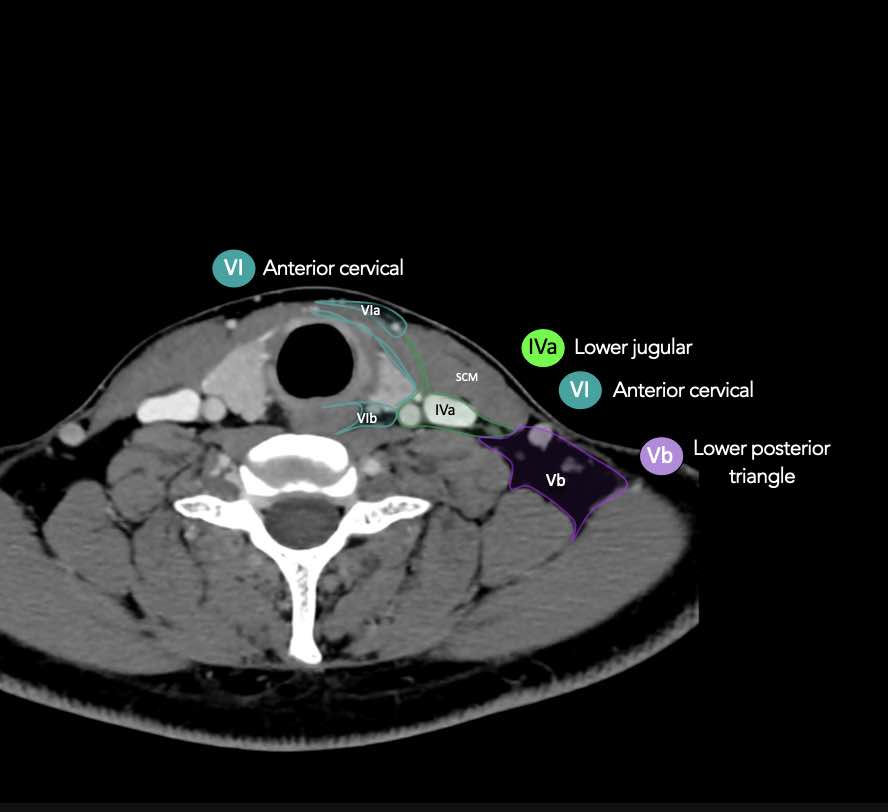

CT Scan Mặt Cắt Ngang (Axial CT)

Các lát cắt CT mặt phẳng ngang tương ứng với hình minh họa tổng quan.

Các lát cắt CT mặt phẳng ngang với hình ảnh chi tiết hơn.

Nhấp vào hình ảnh để phóng to.

IV – Tĩnh mạch cảnh dưới và hố thượng đòn trong

Ranh giới giữa tầng IVa và IVb được xác định tùy ý tại vị trí 2 cm phía trên khớp ức đòn.

Tầng IVa

Các hạch này có nguy cơ chứa di căn từ các ung thư hạ hầu, thanh quản, tuyến giáp và thực quản cổ.

VI – Cổ trước

Tầng này chứa các hạch tĩnh mạch cảnh trước nông (tầng VIa) và các hạch sâu hơn bao gồm hạch trước thanh quản, trước khí quản, cạnh khí quản và hạch thần kinh thanh quản quặt ngược (tầng VIb).